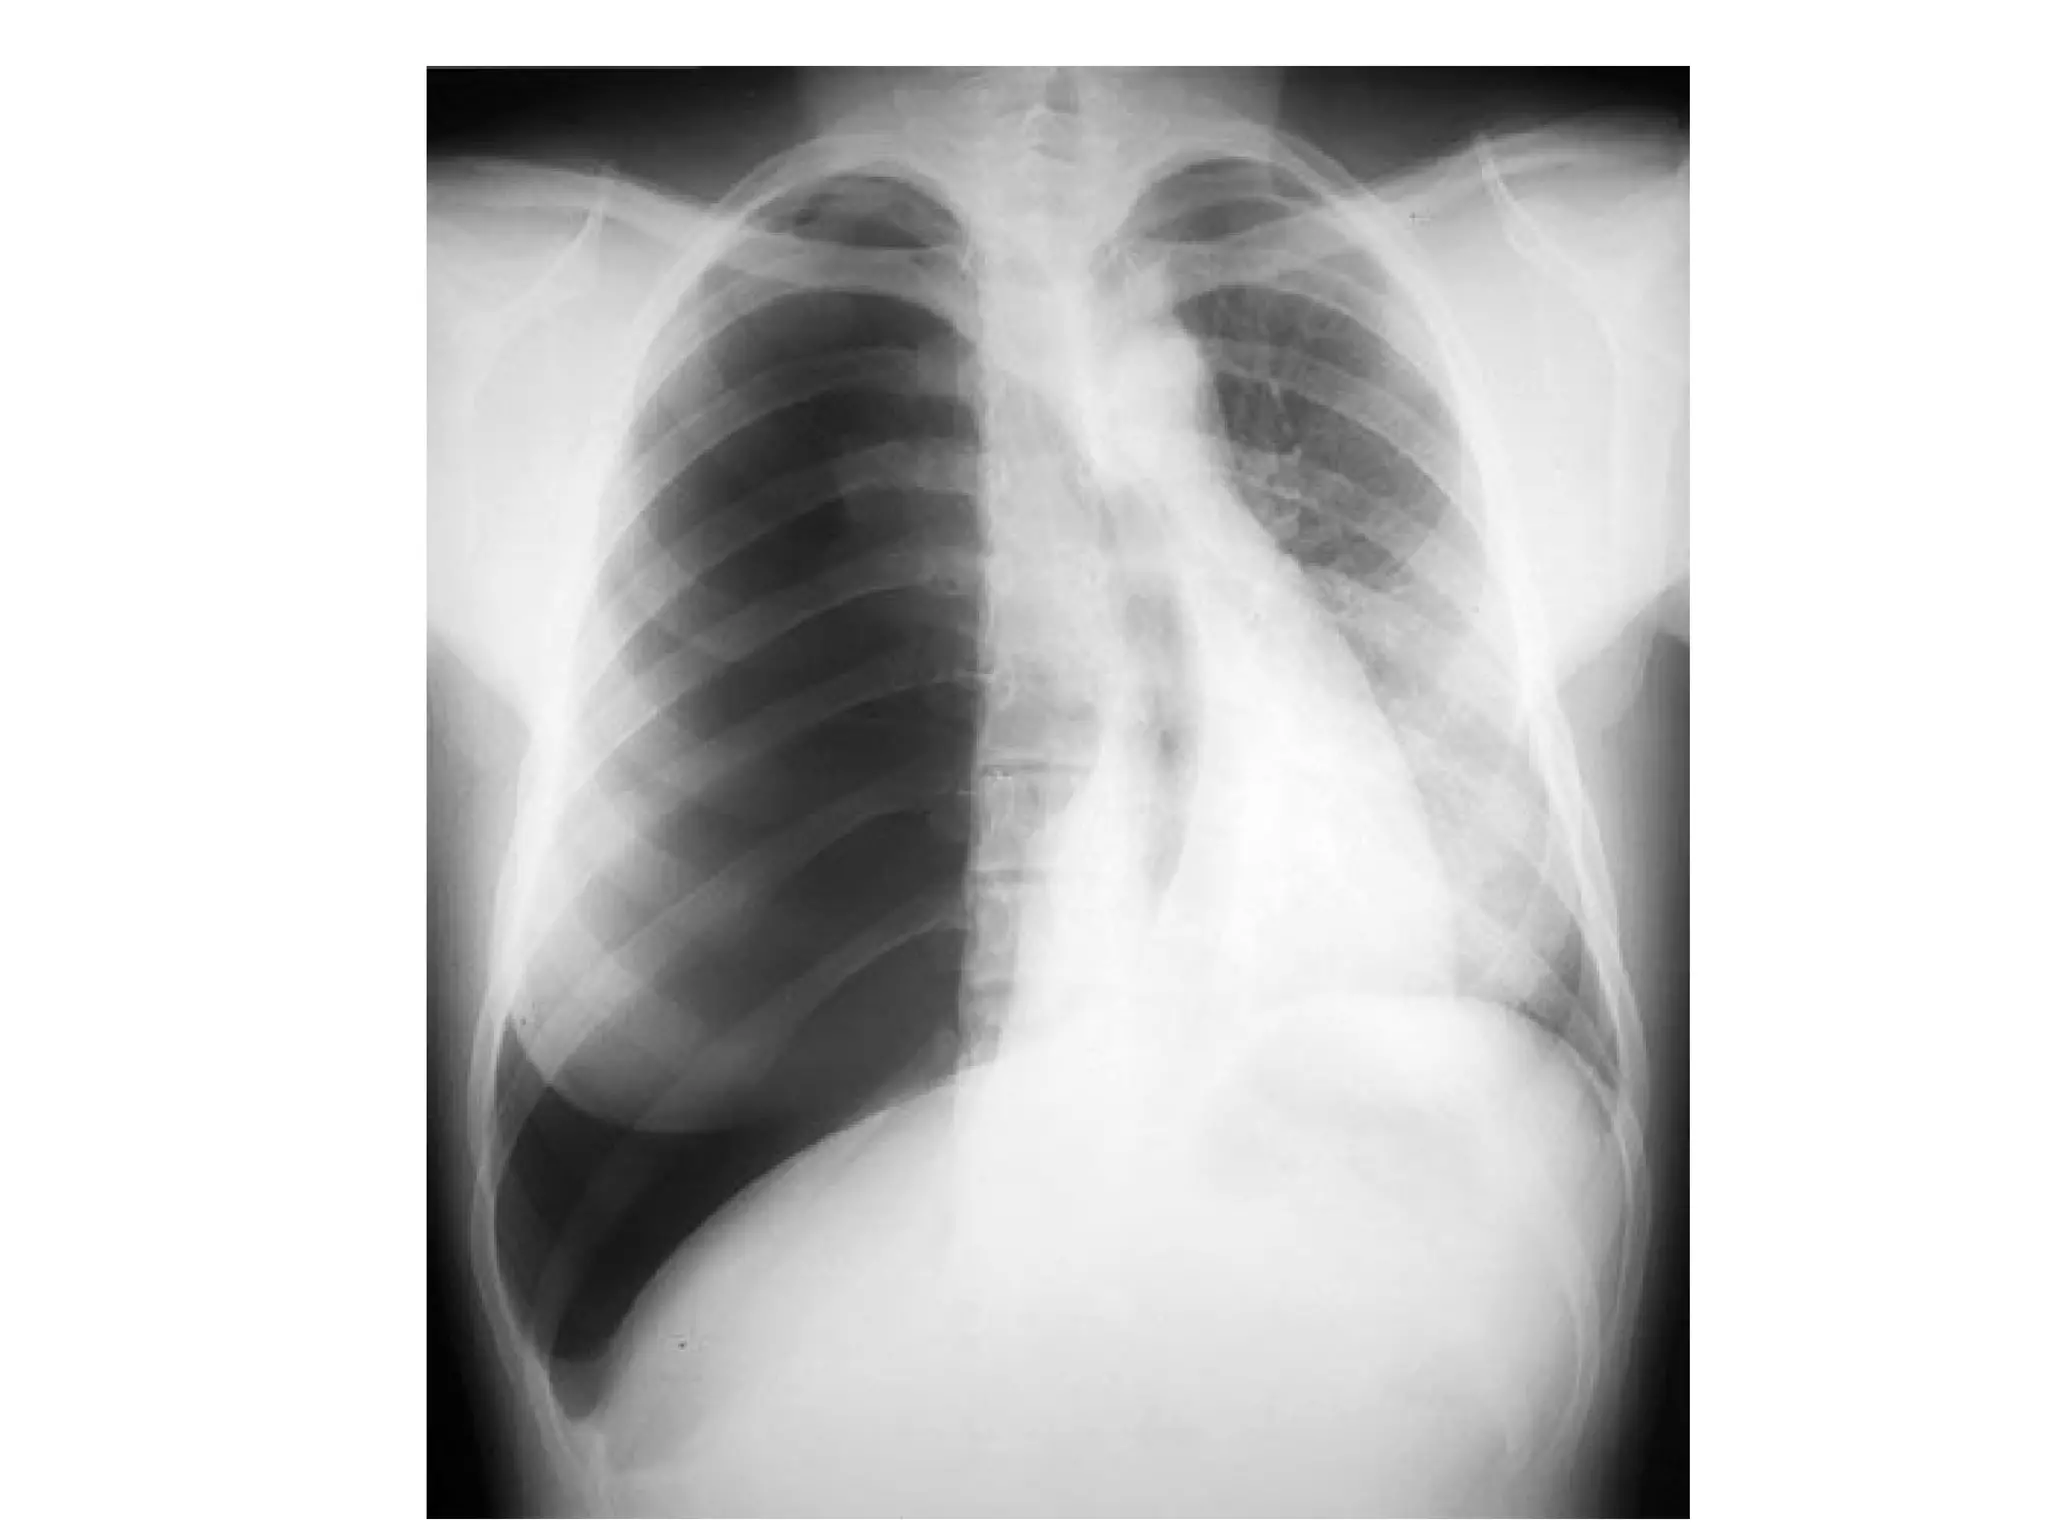

MANAGEMENT

• Search for ‘lethal six’. Diagnosis is clinical.

• Massive haemothorax – tachpnoea, decreased

• Chest – review primary survey and perform